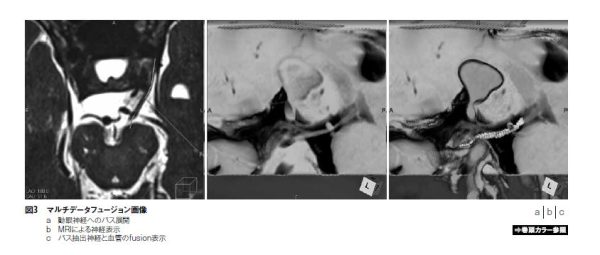

dilation/erosionはziostation2での“盛り上げる/削る” ツールであり、脳神経の抽出にとても有効である。脳神経は細いもので1mm程度の構造であり、MRIが描出に優れる。脳動脈瘤では発生箇所や大きさによって視神経や動眼神経が圧排され、神経症状を来す。したがって、こうした動脈瘤の治療では、術前画像において脳神経の描出も求められる。ziostation2で脳神経を抽出する手順の第一は、同定と明瞭な走行表示である。脳神経は多くが直線的な構造であるため、3軸の回転によって神経を明瞭に描出させる。この後、神経に沿ってパスを引く作業を行う。そして、パスを“盛り上げる”、もしくはパスを“削る”→ “反転決定” によって、簡便に神経の抽出が実現できる。神経圧排症例では、動脈瘤など病変構造に圧排されている脳神経の形状に追従してパスを引いて行けば抽出が可能である。また“マルチデータフュージョン” でCT、MRIの画像デ―タを展開する事で、脳神経と血管などを含む構造も明瞭に立体表示が可能となる(図3)。